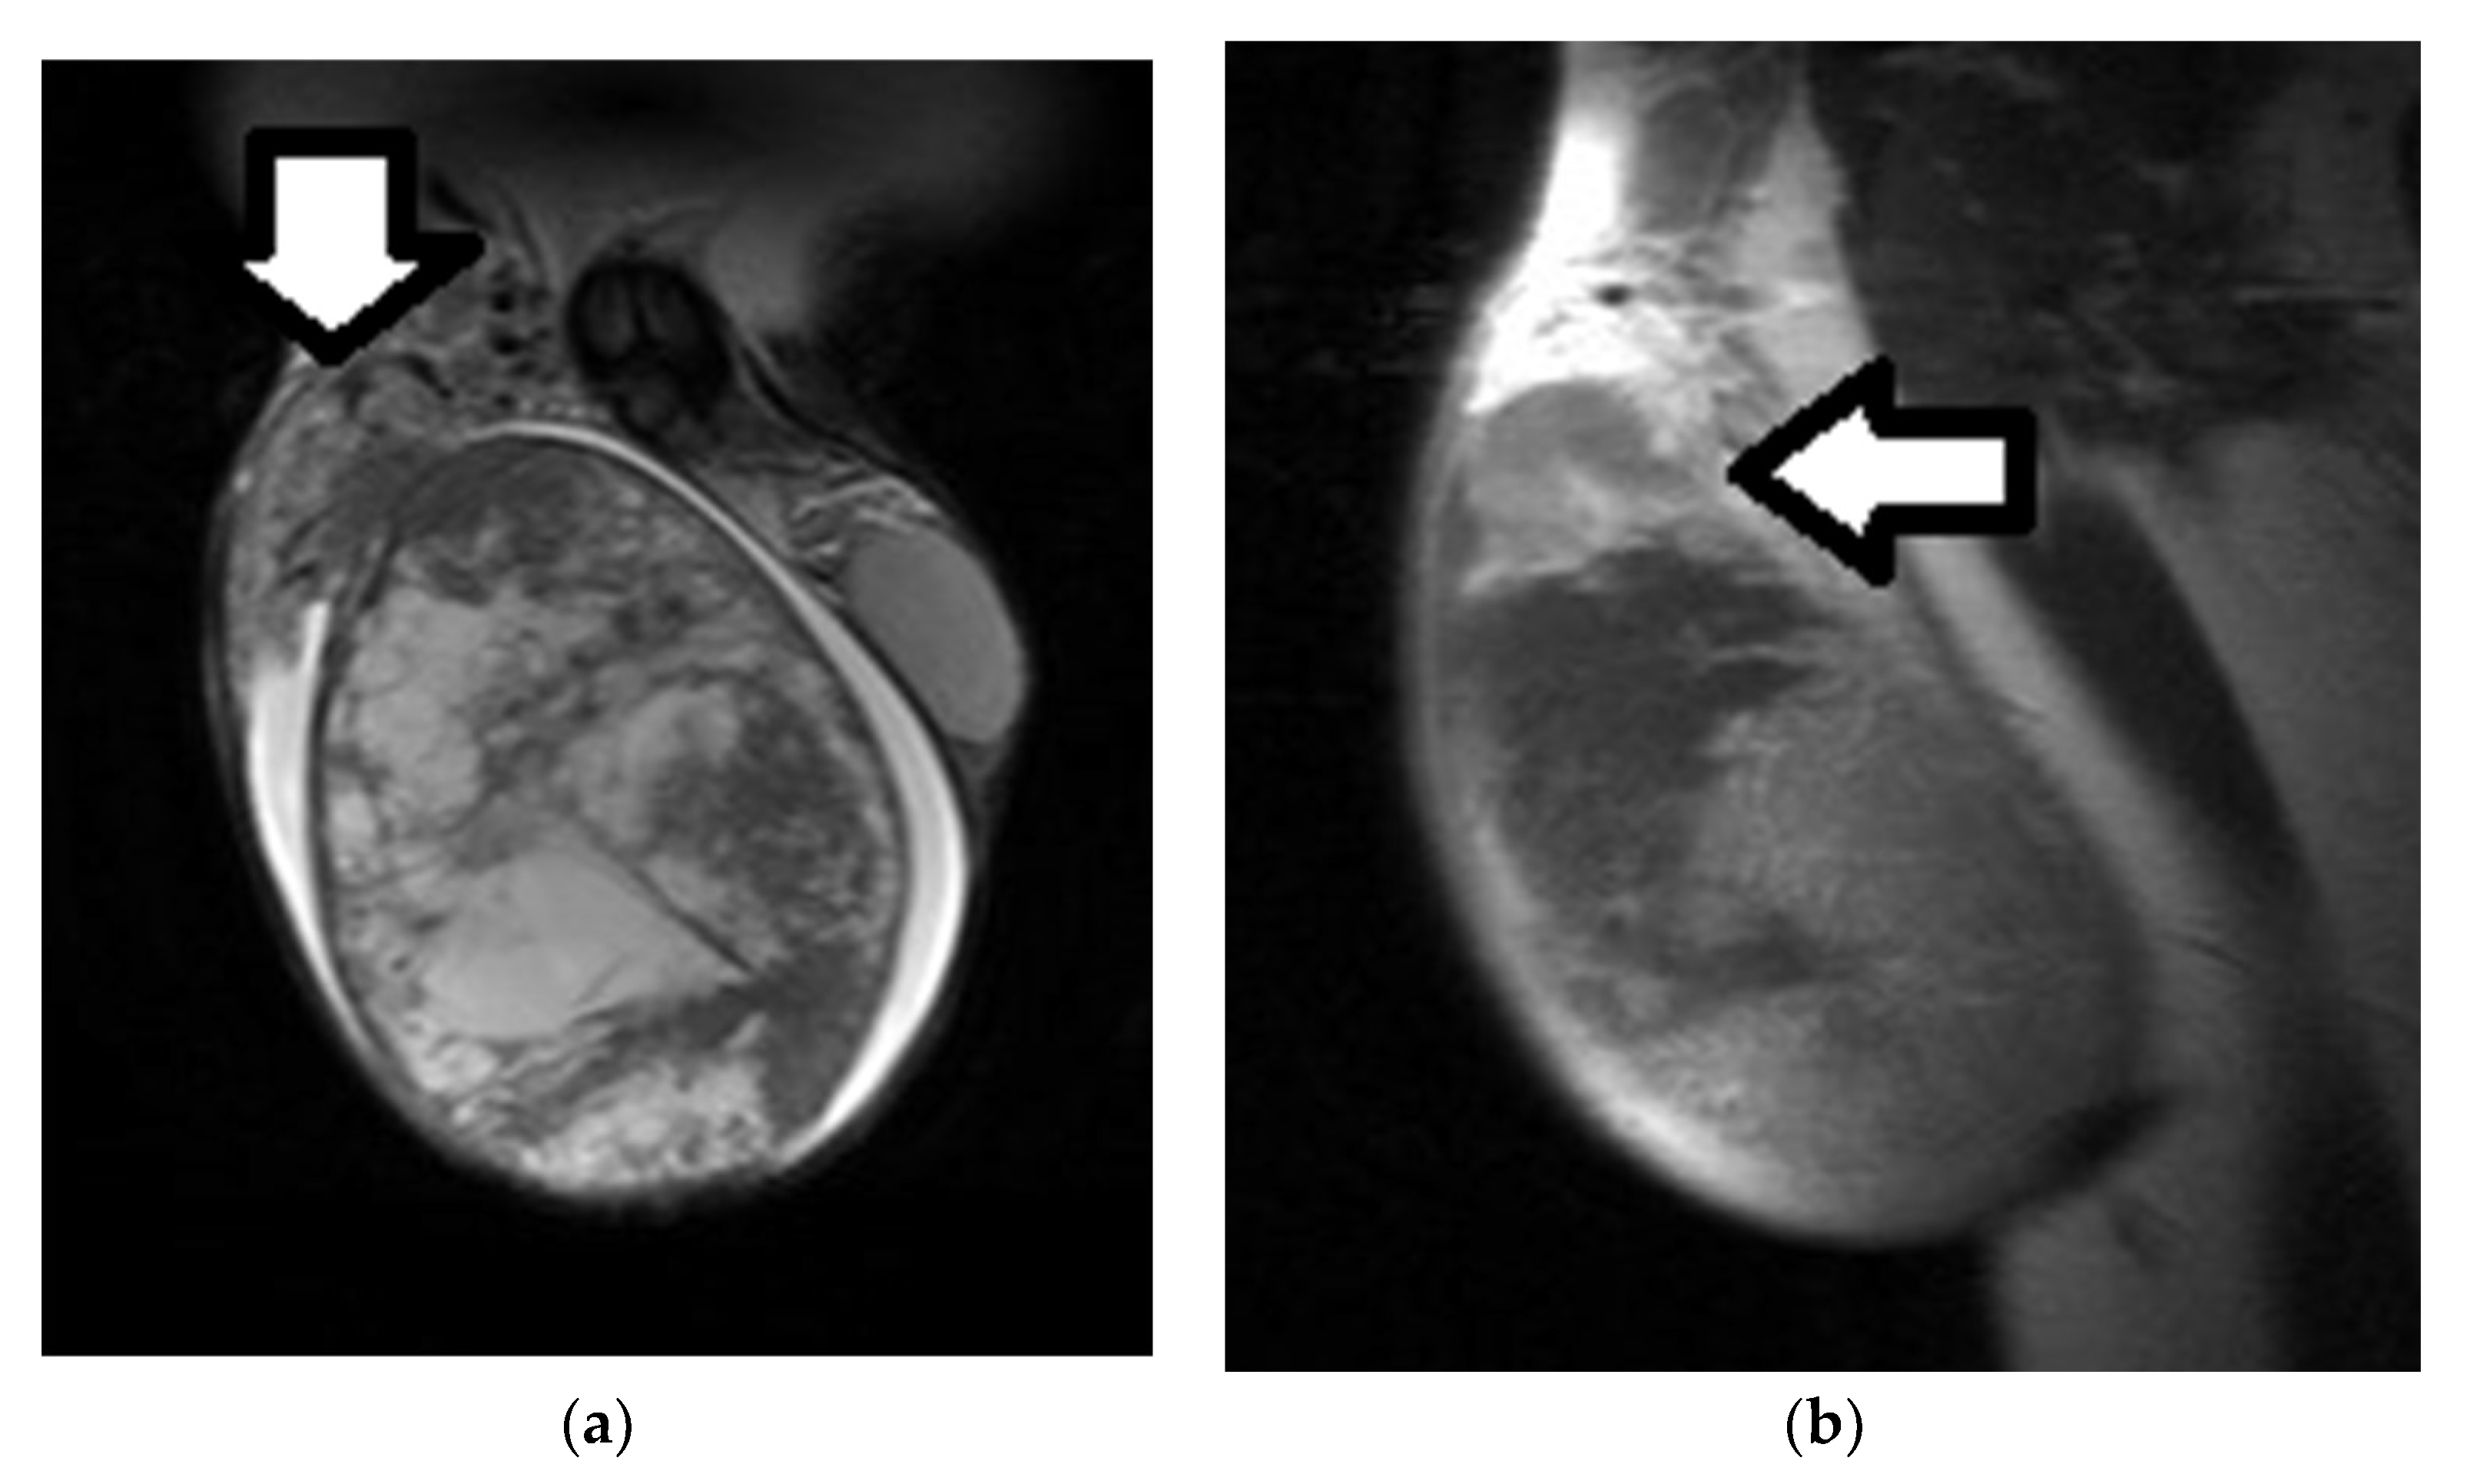

6. Local Staging of TGCTs

3.1. MRI Findings of TGCTs